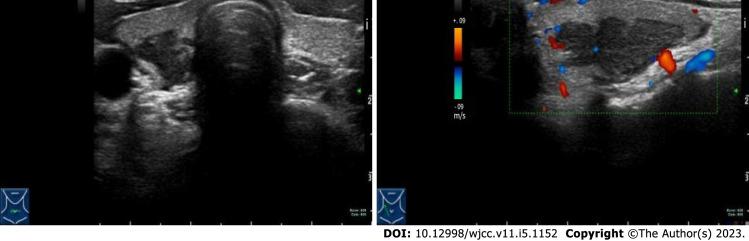

误诊为甲状腺恶性肿瘤的朗格汉斯细胞组织细胞增多症:一例报告。

Langerhans cell histiocytosis misdiagnosed as thyroid malignancy: A case report.

CASE SUMMARY

We report a young woman with a thyroid nodule. Thyroid malignancy was suggested by fine needle aspiration, but she was eventually diagnosed with multisystem LCH, thus avoiding thyroidectomy.

病例摘要

我们报告一名患有甲状腺结节的年轻女性。细针穿刺提示甲状腺恶性肿瘤,但她最终被诊断为多系统LCH,从而避免了甲状腺切除术。